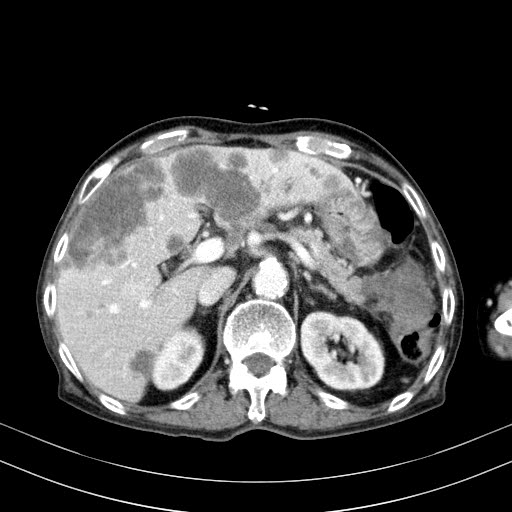

횡단면 영상에서 종괴는 췌장꼬리를 내측으로, 대장을 뒤쪽으로 밀면서 장기를 침범하고 있습니다. 간 내에 여러개의 전이암도 함께 관찰됩니다. 해당 종괴가 정확히 어디에 위치한 것인지 CT만 가지고는 구분하기 어려워 초음파영상을 추가로 시행해 보았습니다.

시행한 초음파영상에서 얻은 췌장의 횡단면 영상입니다.